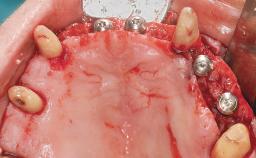

Immediate Loading of Six Implants in the Maxilla and Final Restoration with a Full-Arch CAD/CAM Zirconia FDP

A 63-year-old male patient was referred for a consultation and treatment of partial edentulism in the maxilla. The patient presented with residual anterior teeth and declined a partial removable prosthesis. He reported that the maxillary posterior teeth had been extracted due to mobility and periodontal disease two months before the consultation. The patient’s chief complaint was that his residual maxillary teeth were mobile and that he was unable to chew. The patient’s desire was a stable and comfortable fixed maxillary rehabilitation. The patient was a light smoker (fewer than 10 cigarettes/ day), and his medical history was without significant findings. He was not on any regular medication at the time of consultation. The extraoral examination revealed a normal physiognomy with a correct distribution of the facial thirds. The patient presented a low lip line, and the transition line between teeth and soft tissues was not exposed during a forced smile.

Bone Augmentation Horizontal|Simultaneous

Defining Characteristics Fully edentulous upper jaw to be rehabilitated with four or more implants

Modality 6+ implants with immediate loading